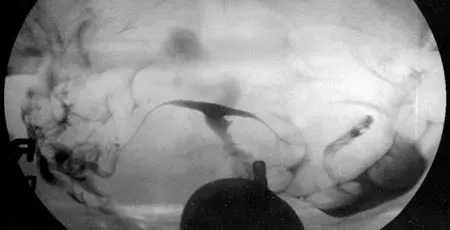

- Hysterosalpingogram or HSG – an x-ray of the uterus and fallopian tubes may reveal a unicornuate, septate, or bicornuate uterus. Note that HSG is not able to show whether the uterine fundus is unified or divided.

Hysterosalpingogram or HSG – an x-ray of the uterus and fallopian tubes may reveal a unicornuate, septate, or bicornuate uterus. Note that HSG is not able to show whether the uterine fundus is unified or divided.

Hysterosalpingogram of a T-shaped uterus from DES exposure